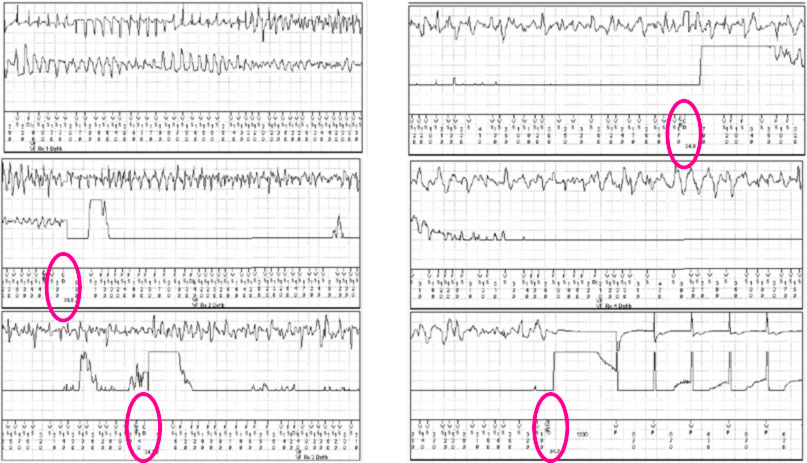

Vanno infine ricercate le aritmie ventricolari, con Holter seriati ed eventualmente loop recorder impiantabile, particolarmente in caso di storia di sincope, e nel caso siano presenti aritmie ventricolari non sostenute si può effettuare lo studio elettrofiusiologico.